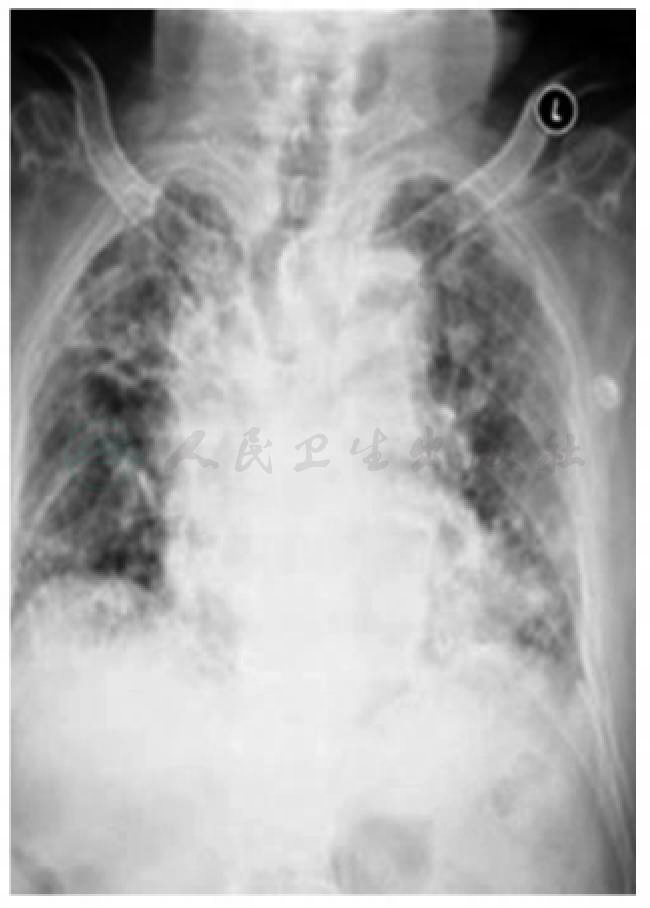

患者术后19个月因肺部感染再次入院治疗,入院检查为肿瘤肺转移并双肺感染,住院不及1个月死亡(图6)。

图6 术后1年胸部X线片